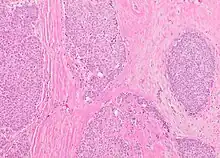

The microscopic histopathology of typical PDCIS lesions (refer to adjacent high-power photomicrograph) prepared with a hematoxylin and eosin stain consists of mammary ducts that have papillary fronds (i.e. thin, finger-like or leaf-like structures) lined with one or several layers of neoplastic, columnar-shaped epithelial cells (i.e. tall, narrow cells with their nuclei close to the site of their ductal attachment).[4] The fronds have branching fibrovascular cores. Epithelial cells lining the fronds' inner surfaces commonly form solid, cribriform (i.e. large nests of cells perforated by many rounded, variably sized spaces), or micro-papillary patterns. There may be a second population of epithelial cells lining the papillae that have abundant clear cytoplasm in addition to the usual neoplastic epithelial cells which line the papillae. These cells, which are not myoepithelial cells, have been termed globoid cells.[7] They have eosinophilic cytoplasm (i.e. pink or red cytoplasm due to its uptake of eosin stain).[6] PDCIS tumors with these cells have been termed dimorphic variants of PDCIS.[3] Myoepithelial cells are typically present at the periphery of the fronds but absent within the involved ducts.[4][7] The presence of a fibrous capsule and/or absence of peripherally located myoepithelial cells are strong indicators that the tumor is an ESP rather than a PDCIS.[3] PDCIS tissues may also contain areas of "Comedo-type necrosis", i.e. areas where dead cells have accumulated.[6]

Microscopic histopathological analyses of SPC lesions (refer to adjacent high-power photomicrograph) generally show tumors with multiple circumscribed nodules of expanded ducts filled with neoplastic epithelial cells which may appear spindle-shaped or plasma cell-like, have red to pink cytoplasm due to the uptake of eosin after staining with hematoxilin & eosin, and eccentrically-placed nuclei. Rarely, signet ring-shaped cells are present. The tumors may have cystic and hemorrhagic areas. Myoepithelial cells are found within and at the periphery of these tumors. The papillary architecture seen in the other SCB types is in general not apparent; rather, pseudo-rosettes (i.e. radial arrangements of neoplastic cells around small blood vessel) and nuclear palisading (i.e. parallel arrangements of the nuclei in rows of tumors that resembles picket fences) around stromal cores (i.e. supporting tissues) may be seen. SPC tumor tissues typically (>50% of cases) have areas of neuroendocrine differentiation. The presence of these areas strongly supports the diagnosis of SPC.[21] The signet ring-shaped cells in these tumors contain cytoplasmic mucin-containing vacuoles which push their cells' nuclei to one side.[10] Mucin may also occur outside of cells in these lesions. The presence of signet ring-shaped cells bearing mucin-containing vacuoles with or without extracellular mucin strongly supports the diagnosis of SPC. SPC is considered invasive when the tumor nests have a characteristic jigsaw growth pattern with ragged and irregular margins with the loss of myoepithelial cells at the site(s) of invasion.[21] Rarely, invasive SPC occurs with nearby invasive carcinoma of NST, lobular carcinoma, cribriform carcinoma, or tubular carcinoma breast tumors.[3]

Since many of the earlier published cases of IPC actually appear to be variants of invasive EPC or SPC, there is little consistent pathological data on IPC.[7] Studies on the microscopic histopathology of IPC have reported finding (refer to the adjacent high-power photomicrograph): 1) blunt papillae or ductal structures consisting of neoplastic epithelial cells surrounding a fibrovascular core;[1] 2) papillae located in dilated ducts and variably sized microcysts plus foci of necrosis (i.e. dead cells);[4] 3) tumors totally dominated by fibrovascular cores covered with neoplastic epithelium cells;[3] and 4) tumors showing >90% papillary morphology invading nearby breast tissue and/or sub-mammary chest muscles.[22] Studies do agree that IPC tumors have, by definition, one or more sites that have invaded nearby breast and/or muscle tissue, lack myoepithelial cells at their invasion sites, and generally lack a peripheral fibrous capsule; these features are important for diagnosing IPC.[6][7][20][22] Rarely, ductal carcinoma in situ lesions are present near IPC.[3] A retrospective histopathological analysis of the tumor tissues in 1,147 individuals with IPC reported that 89.3%, 83.4%, and 2.4% of the cases had tumor cells which respectively expressed the estrogen receptor, progesterone receptor, and HER2/neu protein (however, 46.4% of the cases were not tested for the HER2/neu).[1] In a second histopathological study of 44 individuals diagnosed with IPC, 72.7% had tumor cells that expressed the estrogen receptor, 72.7% had tumor cells that expressed the progesterone receptor, and 13.6% had tumor cells that expressed the HER2/Neu protein.[22] No specific genetic alterations have been as yet been clearly associated with the tumor cells in individuals diagnosed with IPC.[6]